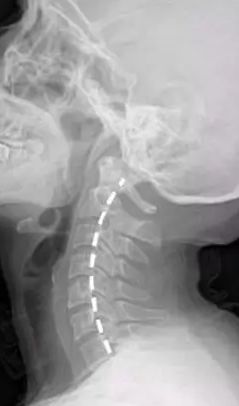

专家答疑颈椎生理曲度变直是什么鬼严重不

400x259 - 10KB - JPEG

颈椎曲度变直\/反张还能恢复正常吗?

640x853 - 41KB - JPEG